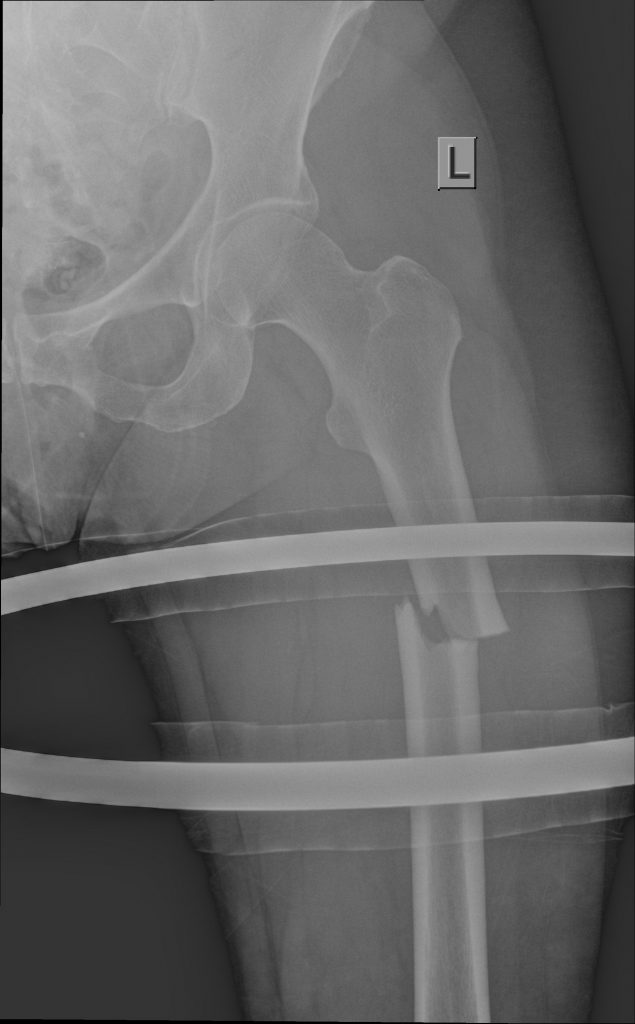

MULTITRAUMA AFTER MOTOR VEHICLE ACCIDENTS

Unfortunately I often see broken bodies after motor vehicle accidents. The injuries sustained are often lifechanging and though the science of orthopedics is advanced, not everything can be repaired to perfection.

Shown here are the x-rays of a young patient who drove at night after taking a few drinks. The fractures are all open and this will be a life changing event for him.